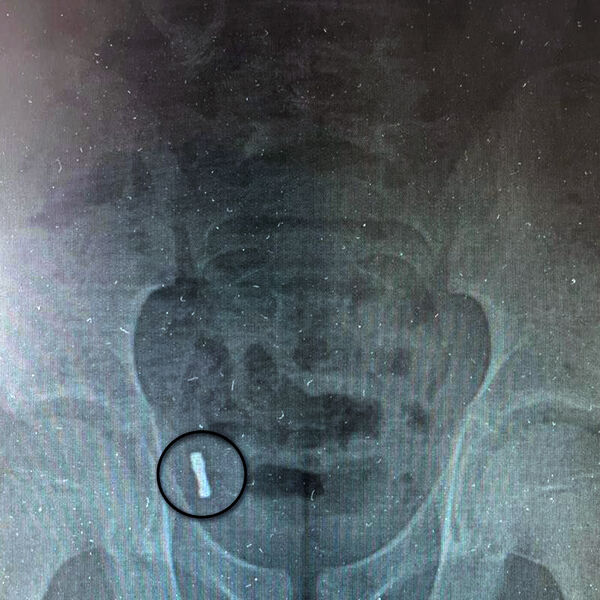

К моменту обращения за помощью инородные предметы мигрировали в аппендикс, что выявил рентген. Медики отметили, что инородные тела крайне редко попадают в аппендикс. За ребенком наблюдали трое суток, после чего приняли решение о проведении операции из-за риска перфорации и развития перитонита.

«Под общим обезболиванием медики провели ревизию брюшной полости, таким образом подтвердив нахождение магнитов в аппендиксе. Специалисты провели типичную аппендэктомию – удалили аппендикс», — рассказали в пресс-службе.